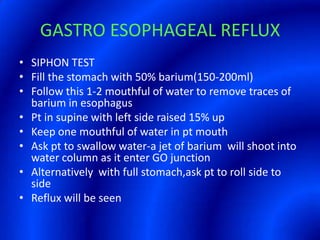

This document provides information about a barium swallow procedure. It begins with an introduction and overview of the embryology and anatomy of the pharynx and esophagus. It then describes the procedure itself, including preparation, technique, views obtained, and indications. Specific conditions that may be examined include pharyngeal and esophageal webs, foreign body impaction, scleroderma, dysphagia, mediastinal masses, and carcinoma. Diagrams are provided to illustrate normal anatomy and various pathological findings.